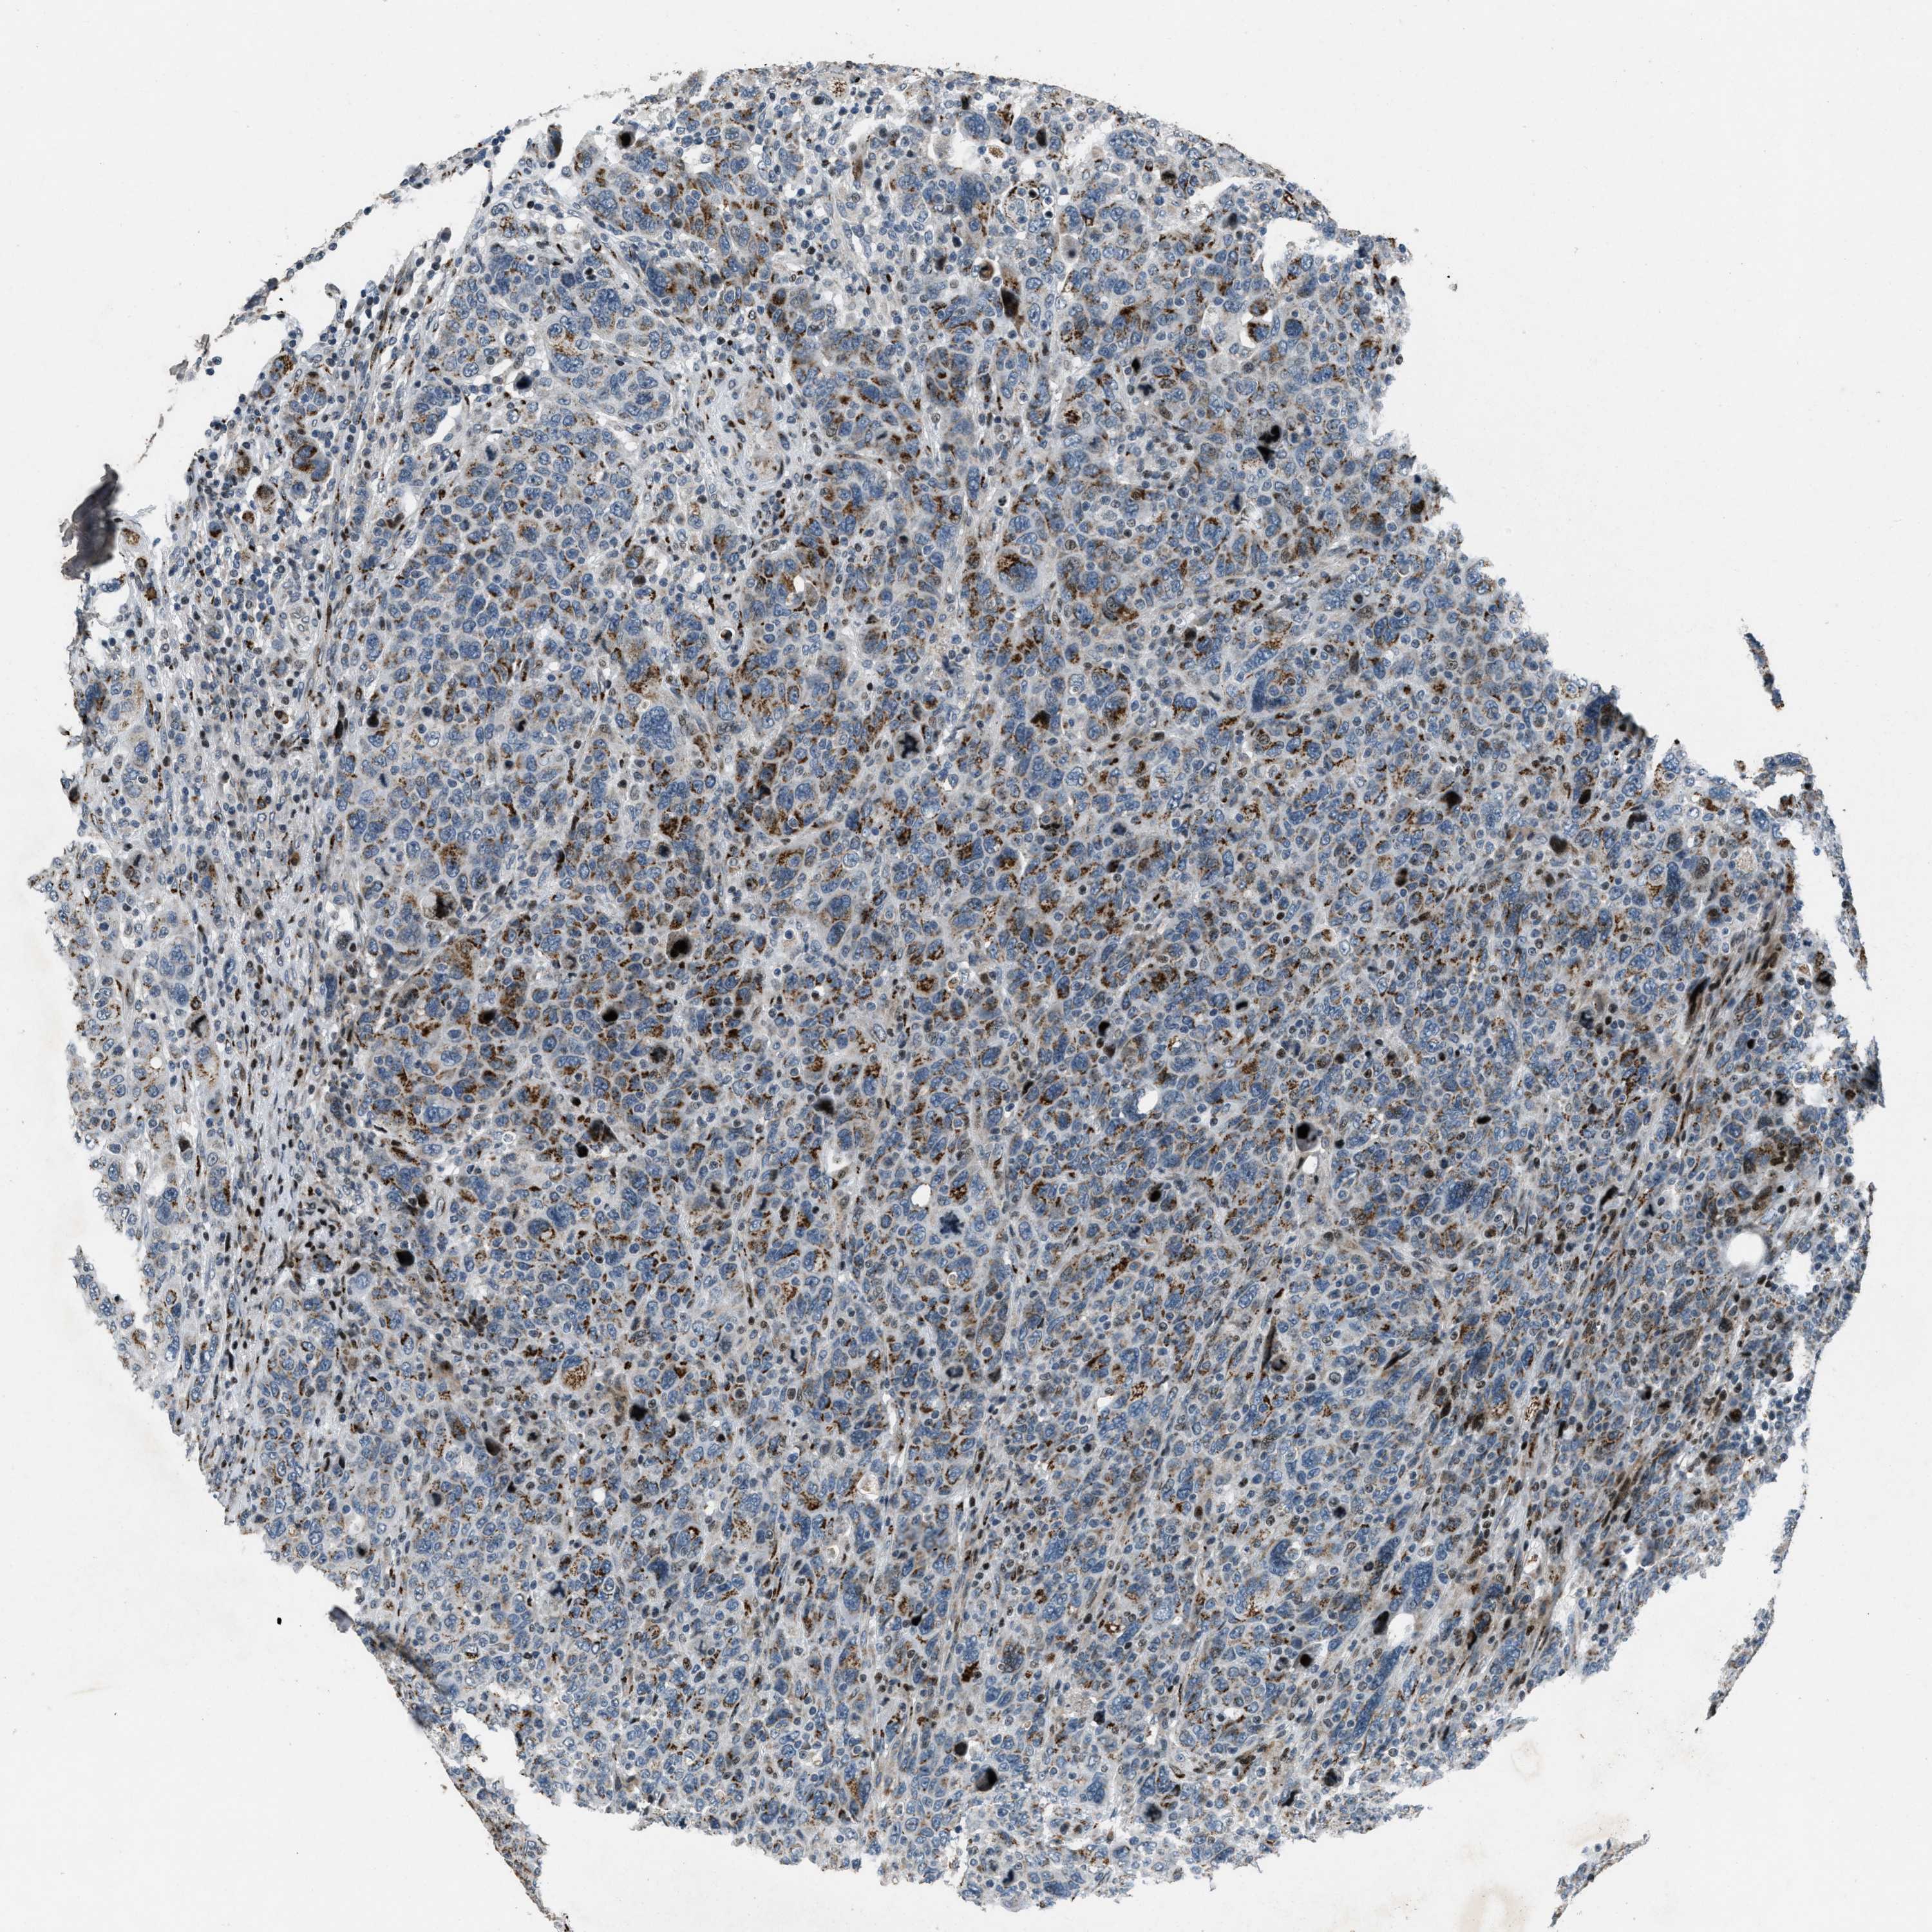

CANCER BREAST CANCER Show tissue menu

BRCA TCGA BRCA VALIDATION PROTEIN EXPRESSION